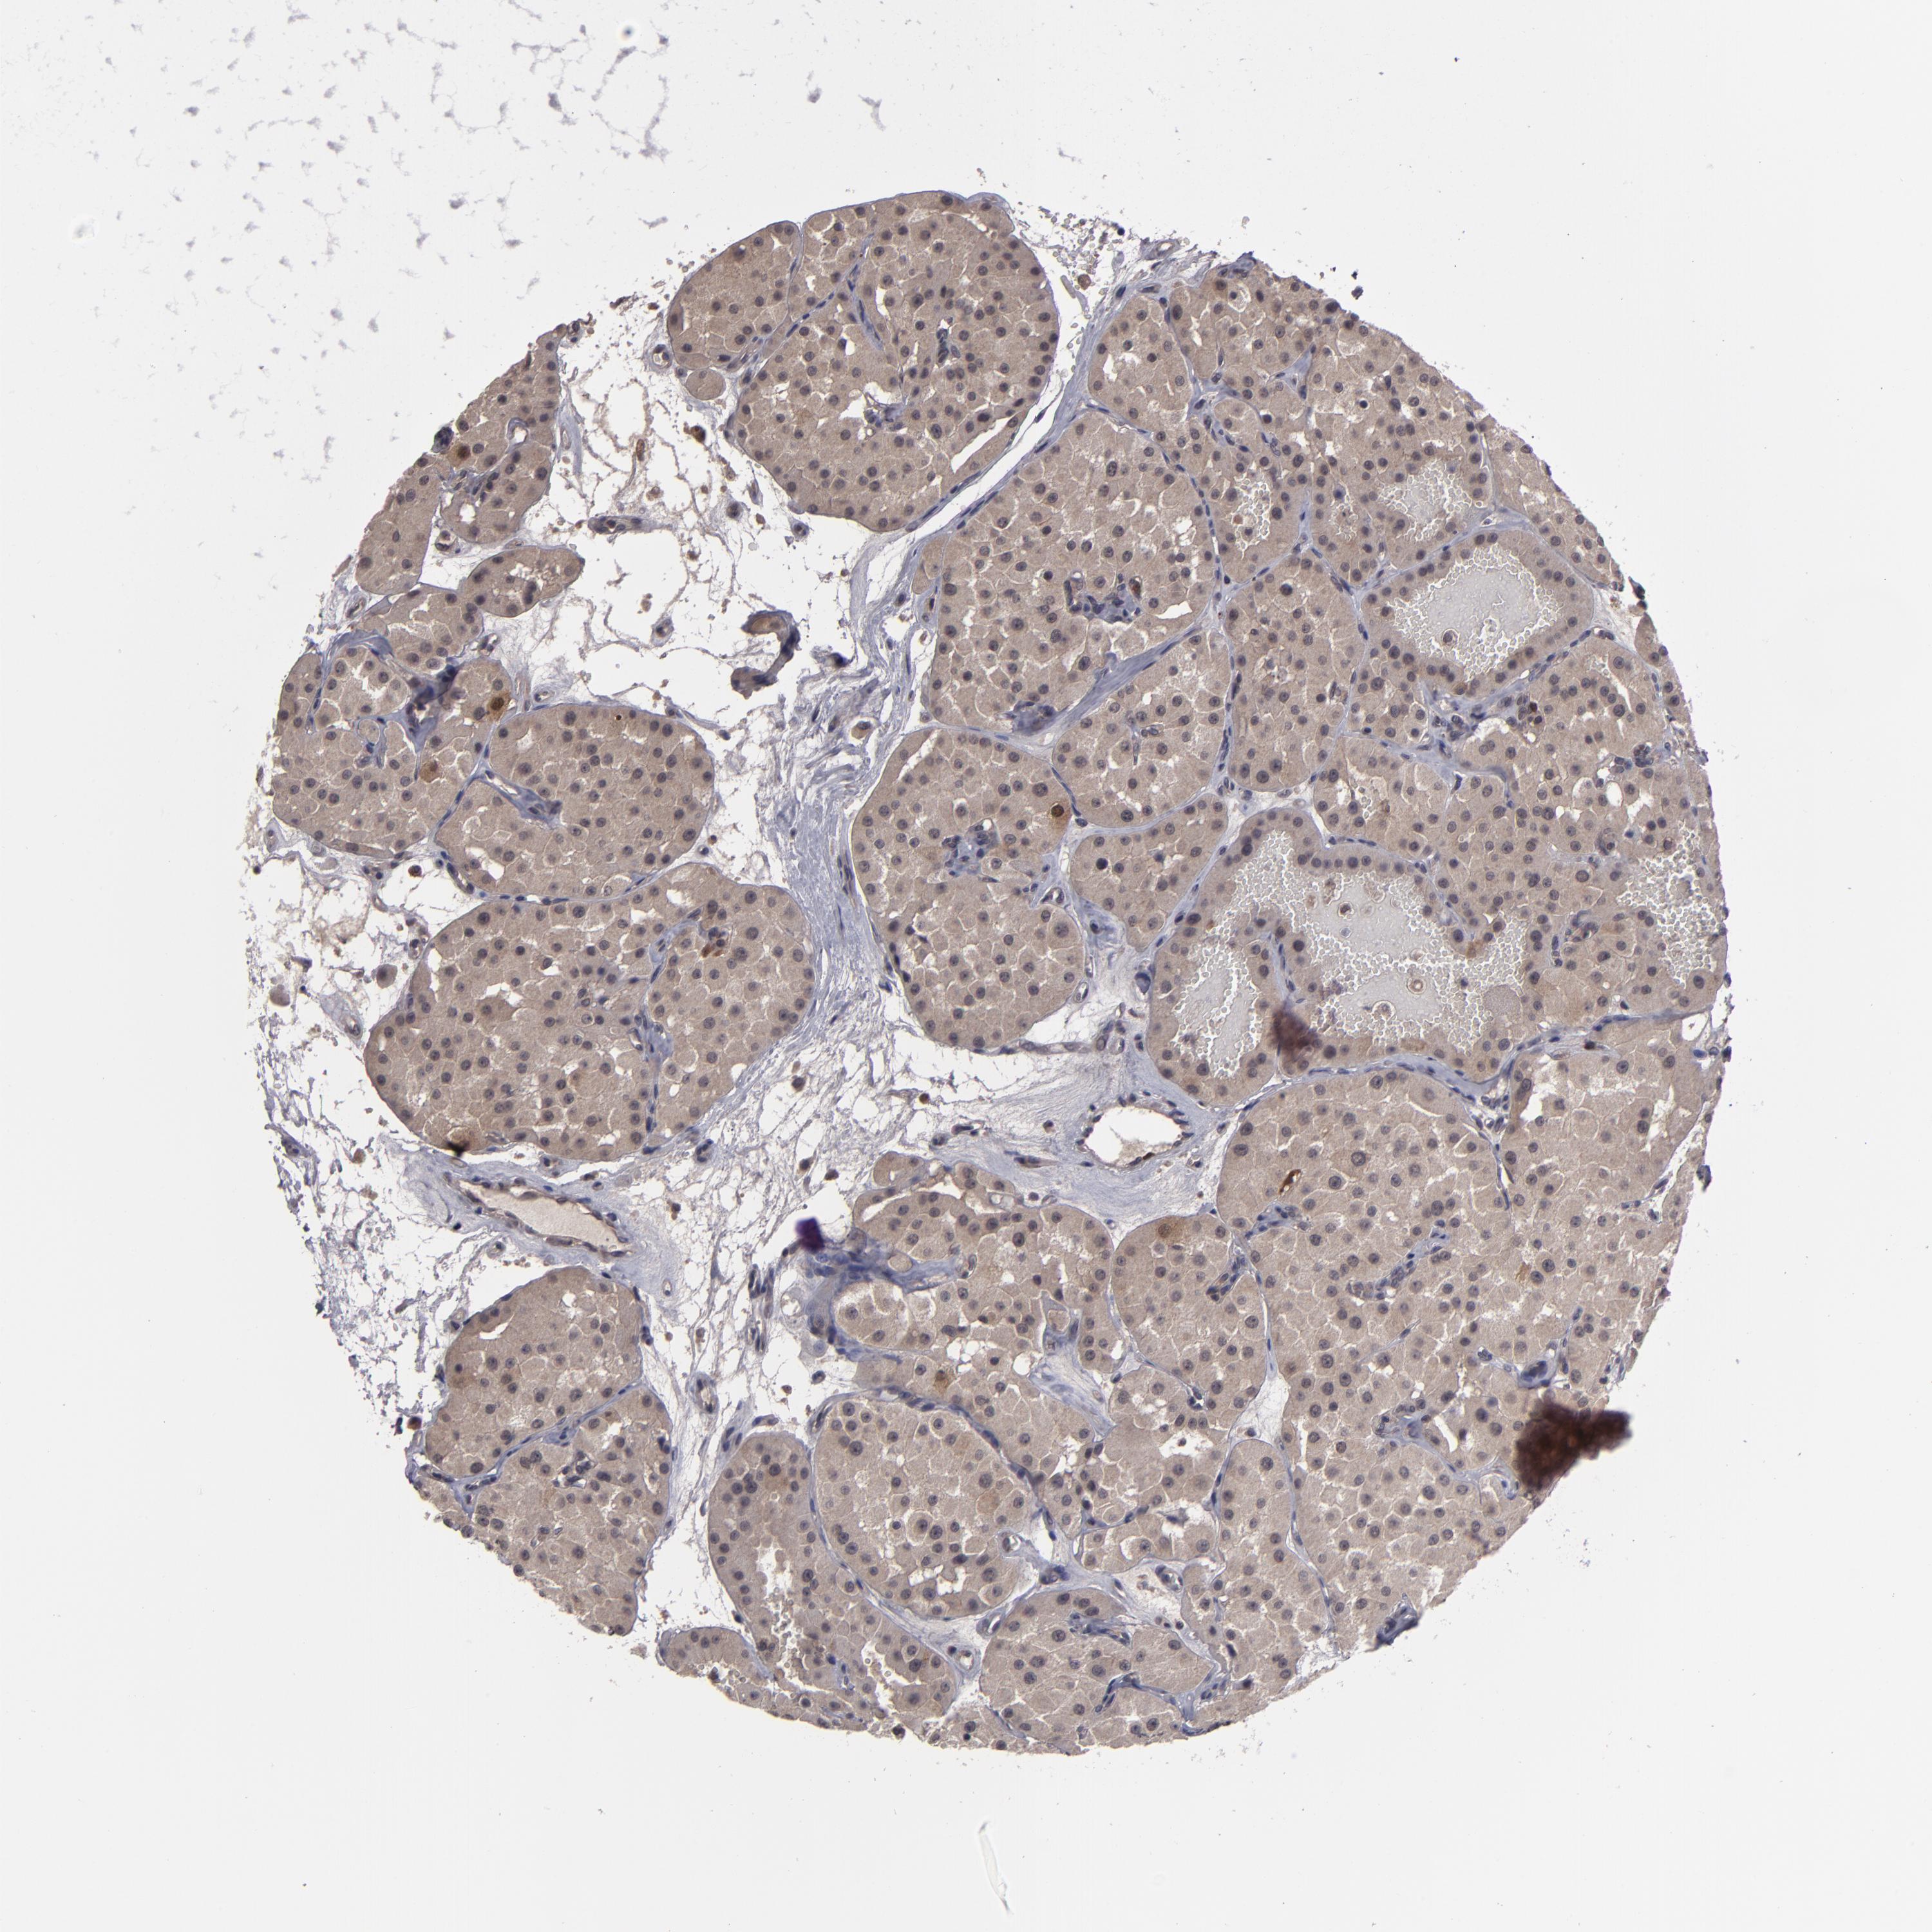

KIDNEY RENAL PAPILLARY CELL CARCINOMA (TCGA) - Interactive survival scatter ploti

The Survival Scatter plot shows the clinical status (i.e. dead or alive) for all individuals in the patient cohort, based on the same data that underlies the corresponding Kaplan-Meier plots. Patients that are alive at last time for follow-up are shown in blue and patients who have died during the study are shown in red.

The x-axis shows the expression levels (FPKM) of the investigated gene in the tumor tissue at the time of diagnosis. The y-axis shows the follow-up time after diagnosis (years). Both axes are complimented with kernel density curves demonstrating the data density over the axes. The top density plot shows the expression levels (FPKM) distribution among dead (red) and alive patients (blue). The right density plot shows the data density of the survived years of dead patients with high and low expression levels respectively, stratified using the cutoff indicated by the vertical dashed line through the Survival Scatter plot. This cutoff is automatically defined based on the FPKM cutoff that minimizes the p-score. The cutoff can be changed by dragging the vertical line or by entering a cutoff value in the square labeled "Current cut-off".

Under the Survival Scatter plot the p-score landscape (black curve; left axis) is shown together with dead median separation (red curve; right axis). Dead median separation is the difference in median mRNA expression between patients who have died with high and low expression, respectively. It is calculated as follows: median FPKM expression of dead patients with high expression - median FPKM expression of dead patients with low expression. This is intended to aid the user in visually exploring custom cutoffs and the associated p-scores and dead median separation.

Individual patient data is displayed and can be filtered by clicking on one or more of the category buttons on the top of the page. Categories describing expression level and patient information include: high, low, alive, dead, female, male and tumor stages. The scale of the x-axis can be toggled between linear and log-scale by clicking on the "x log" button. Mouse-over function shows TCGA ID, patient information and mRNA expression (FPKM) for each patient.

& Survival analysisi

Kaplan-Meier plots summarize results from analysis of correlation between mRNA expression level and patient survival. Patients were divided based on level of expression into one of the two groups "low" (under cut off) or "high" (over cut off). X-axis shows time for survival (years) and y-axis shows the probability of survival, where 1.0 corresponds to 100 percent.

TYMS is not prognostic in Kidney Renal Papillary Cell Carcinoma (TCGA)